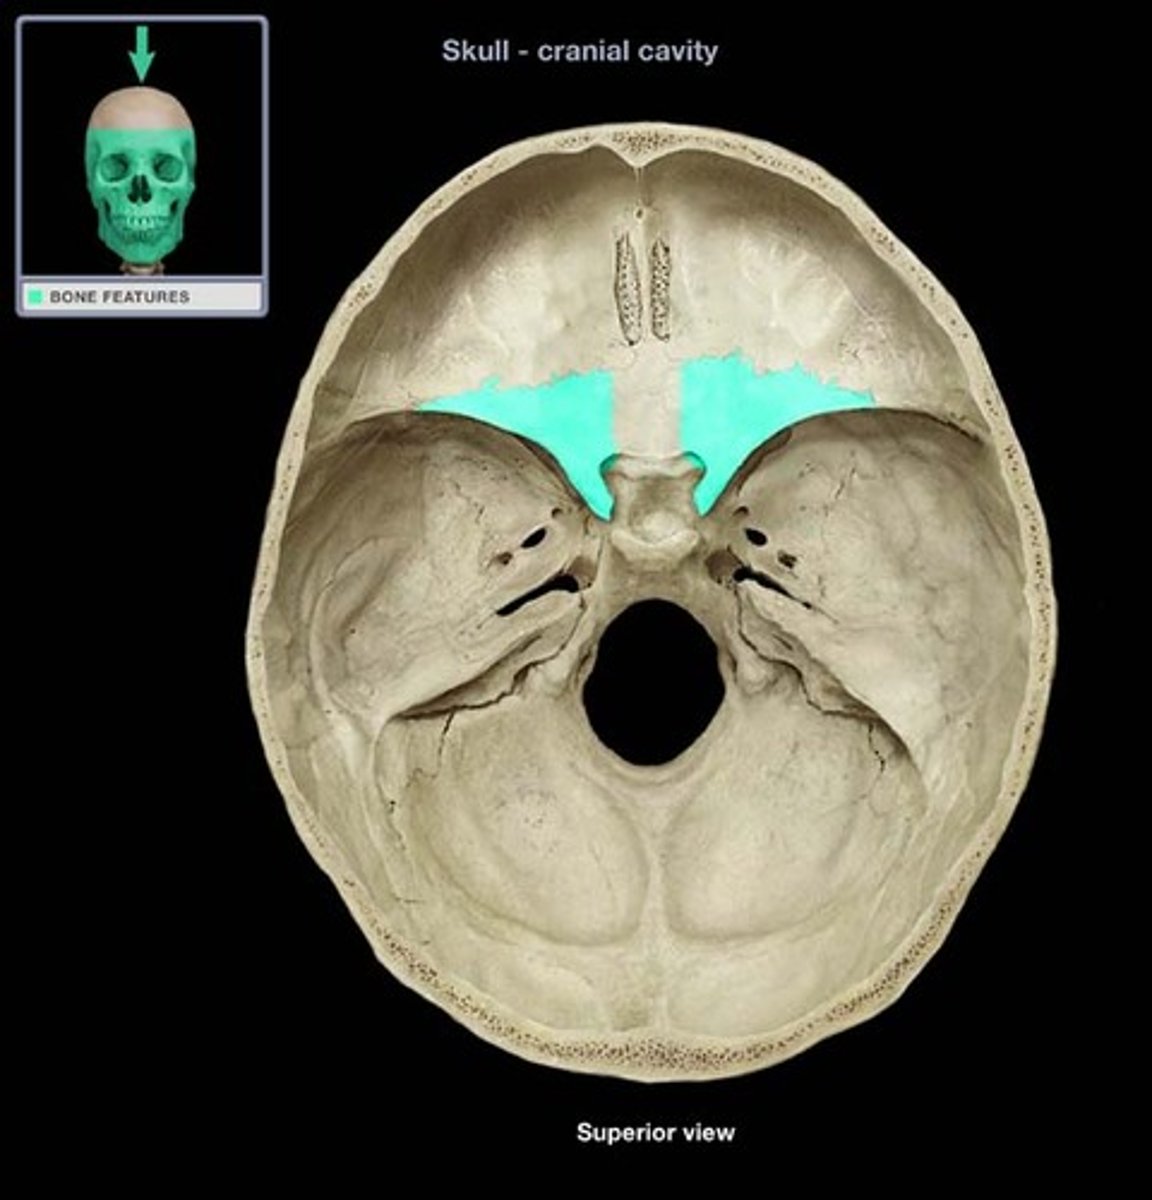

Sphenoid

Name the bone.

sella turcica

Name this structure.

greater wings

Name this structure.

lesser wings

Name this structure.

foramen ovale

Name this structure.

foramen rotundum

Name this structure.

foramen spinosum

Name this structure.

superior orbital fissure

Name this structure.

inferior orbital fissure

Name this structure.

optic canal

Name this structure.